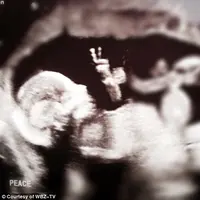

Foto USG diketahui bayinya mengacungkan dua jari seperti memberikan tanda perdamaian 'i come in peace'.

LifestyleJanin Ini Berikan 'Pesan Damai' Lewat Hasil USG

Bayi ini seakan beri pesan perdamaian saat USG dilakukan.